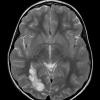

NEOPLASMS (NEURONAL)

DNET (13)